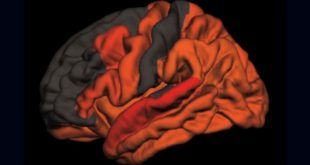

نوروسافاری | یافته های جدید ممکن است به توضیح این کشف شگفت انگیز بپردازند که چرا قرار گرفتن در معرض نور چشمک زن باعث کاهش پلاک آمیلوئید در موش می شود. چندین سال پیش، دانشمندان علوم اعصاب MIT نشان دادند که آنها می توانند به طرز چشمگیری پلاک های آمیلوئیدی …

نوروسافاری | پژوهشگران دانشگاه “ام.آی.تی” در بررسی جدیدی دریافتند که میتوان نشانههای آلزایمر را با کمک تحریک امواج مغزی کاهش داد. به گزارش نوروسافاری از دانشگاه ام. آی. تی، متخصصان علوم اعصاب دانشگاه “ام. آی. تی”(MIT) با قرار دادن موشها در معرض ترکیب منحصر به فردی از نور و صدا، …